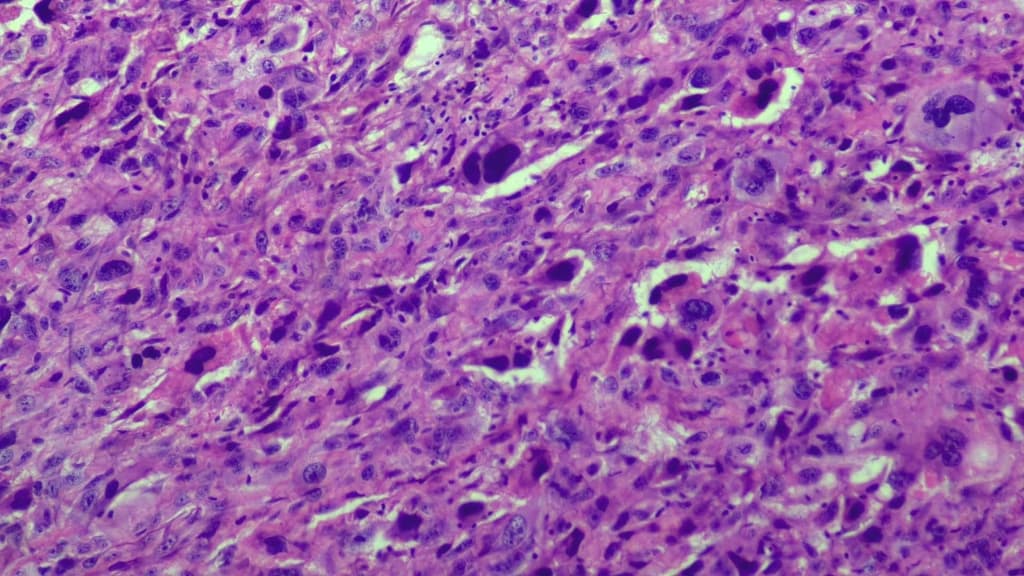

Ca lâm sàng này thể hiện cả di căn phổi có vôi hóa và không vôi hóa từ u sụn xương chi (appendicular osteosarcoma).

Ca lâm sàng này thể hiện cả di căn phổi có vôi hóa và không vôi hóa từ u sụn xương chi. Sự hiện diện của vôi hóa trong tổn thương di căn gợi ý về nguồn gốc u sụn xương. Nốt mô mềm không vôi hóa liền kề với khối vôi hóa có thể là một tổn thương di căn khác hoặc một quá trình lành tính.